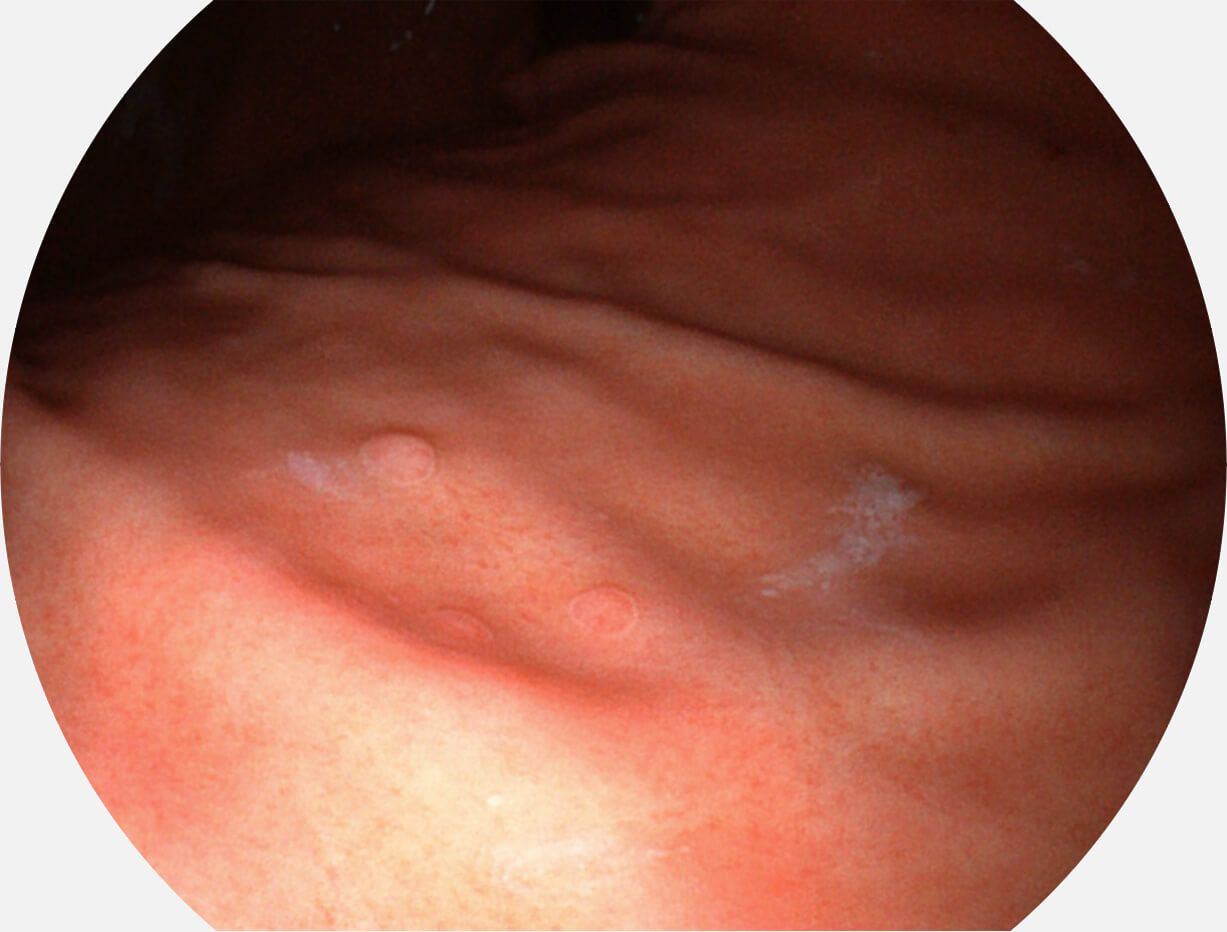

白光图像

VIST图像

强调浅层黏膜结构的同时,保证照明亮度和提升浅层微血管与中层血管颜色对比度,病变边界更清晰。

送水方向与手术器械方向,两者更贴合,能快速冲洗黏膜表面的粘液及出血,发现病变和出血点。